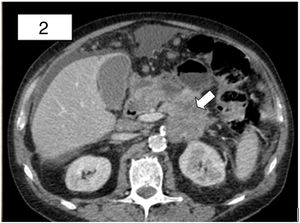

En la tomografía computarizada se halló una neoplasia pancreática, con extensa infiltración local (fig. 2), así como carcinomatosis peritoneal con múltiples implantes, uno a nivel umbilical. El resultado anatomopatológico del nódulo umbilical fue adenocarcinoma de origen pancreático-biliar; confirmando el diagnóstico de nódulo de la hermana María José. Tras ser valorado por el comité multidisciplinar, se inició tratamiento con quimioterapia paliativa.